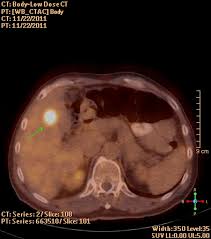

Pancreatic cancer often causes symptoms in the patient's digestive tract.

Pancreatic cancer often causes symptoms in the patient's digestive tract. In many cases, patients with colon cancer have been diagnosed with inflammatory bowel diseases such as ibs, colitis, and diverticulitis. Potent, yet safe — you & your loved one can beat cancer too — learn more here! The findings most specific for diverticulitis were pericolonic. Colorectal cancer may also be misdiagnosed as hemorrhoids, or piles.